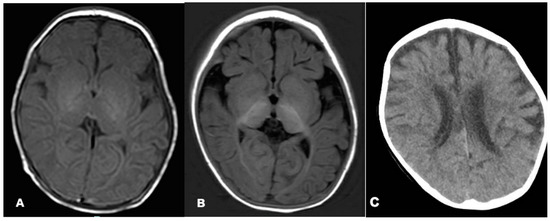

2.2. Neuroimaging and VEEG

| MRI | Hypoplasia of corpus callosum 56% (10/18) |

| Delayed myelination 56% (10/18) | |

| Cerebral and cerebellar atrophy 33% (6/18) | |